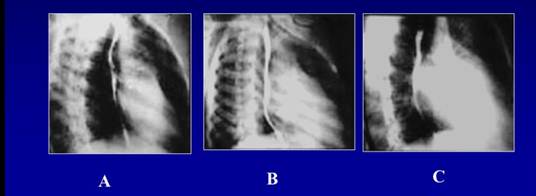

Рис. 8. Рентгенография сердца с контрастированием пищевода в косой проекции (А – норма, В – митральный порок с преобладанием стеноза, С – митральный порок с преобладанием недостаточности)